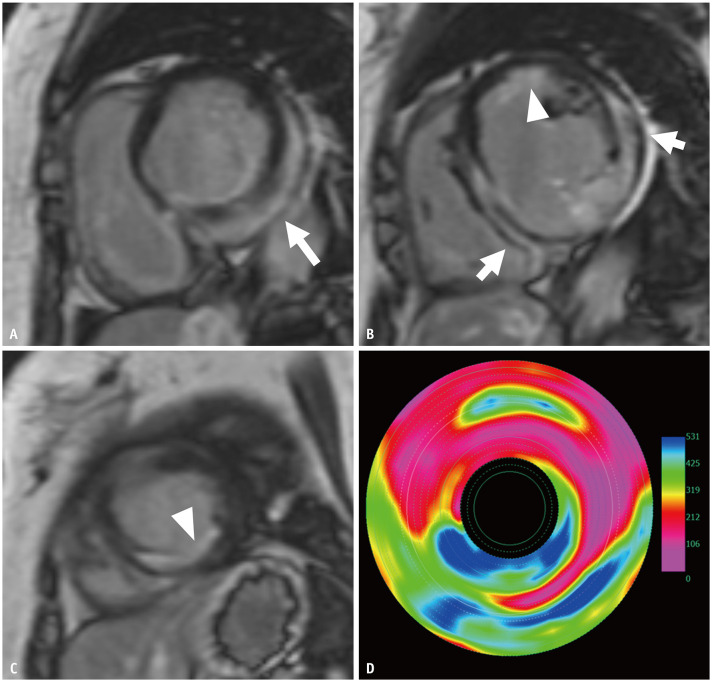

Cardiac sarcoidosis (CS) poses significant diagnostic and therapeutic challenges due to its heterogeneous clinical manifestations and the limitations of conventional diagnostic approaches. Advances in imaging modalities, particularly cardiac magnetic resonance imaging (CMR) and ¹⁸F-fluorodeoxyglucose positron emission tomography (FDG-PET), have revolutionized the evaluation and management of this complex condition. CMR, with its superior spatial resolution and advanced techniques such as late gadolinium enhancement, T1/T2 mapping, and extracellular volume quantification, offers unparalleled insights into myocardial structure and fibrosis. These techniques not only enhance diagnostic accuracy but also provide critical information on disease activity and treatment response. Among these, T2 mapping has emerged as a valuable marker for active inflammation, with high values reliably indicating acute disease states. FDG-PET serves as a complementary modality by detecting active granulomatous inflammation and guiding immunosuppressive therapy. The synergistic integration of CMR and FDG-PET provides a comprehensive approach to diagnosing and monitoring CS, enabling the identification of subclinical disease and the optimization of therapeutic strategies. Furthermore, the incorporation of quantitative biomarkers, such as strain metrics and T2 values, promises to refine disease assessment and management. These advancements have the potential to transform the paradigm of CS care, ultimately improving patient outcomes.